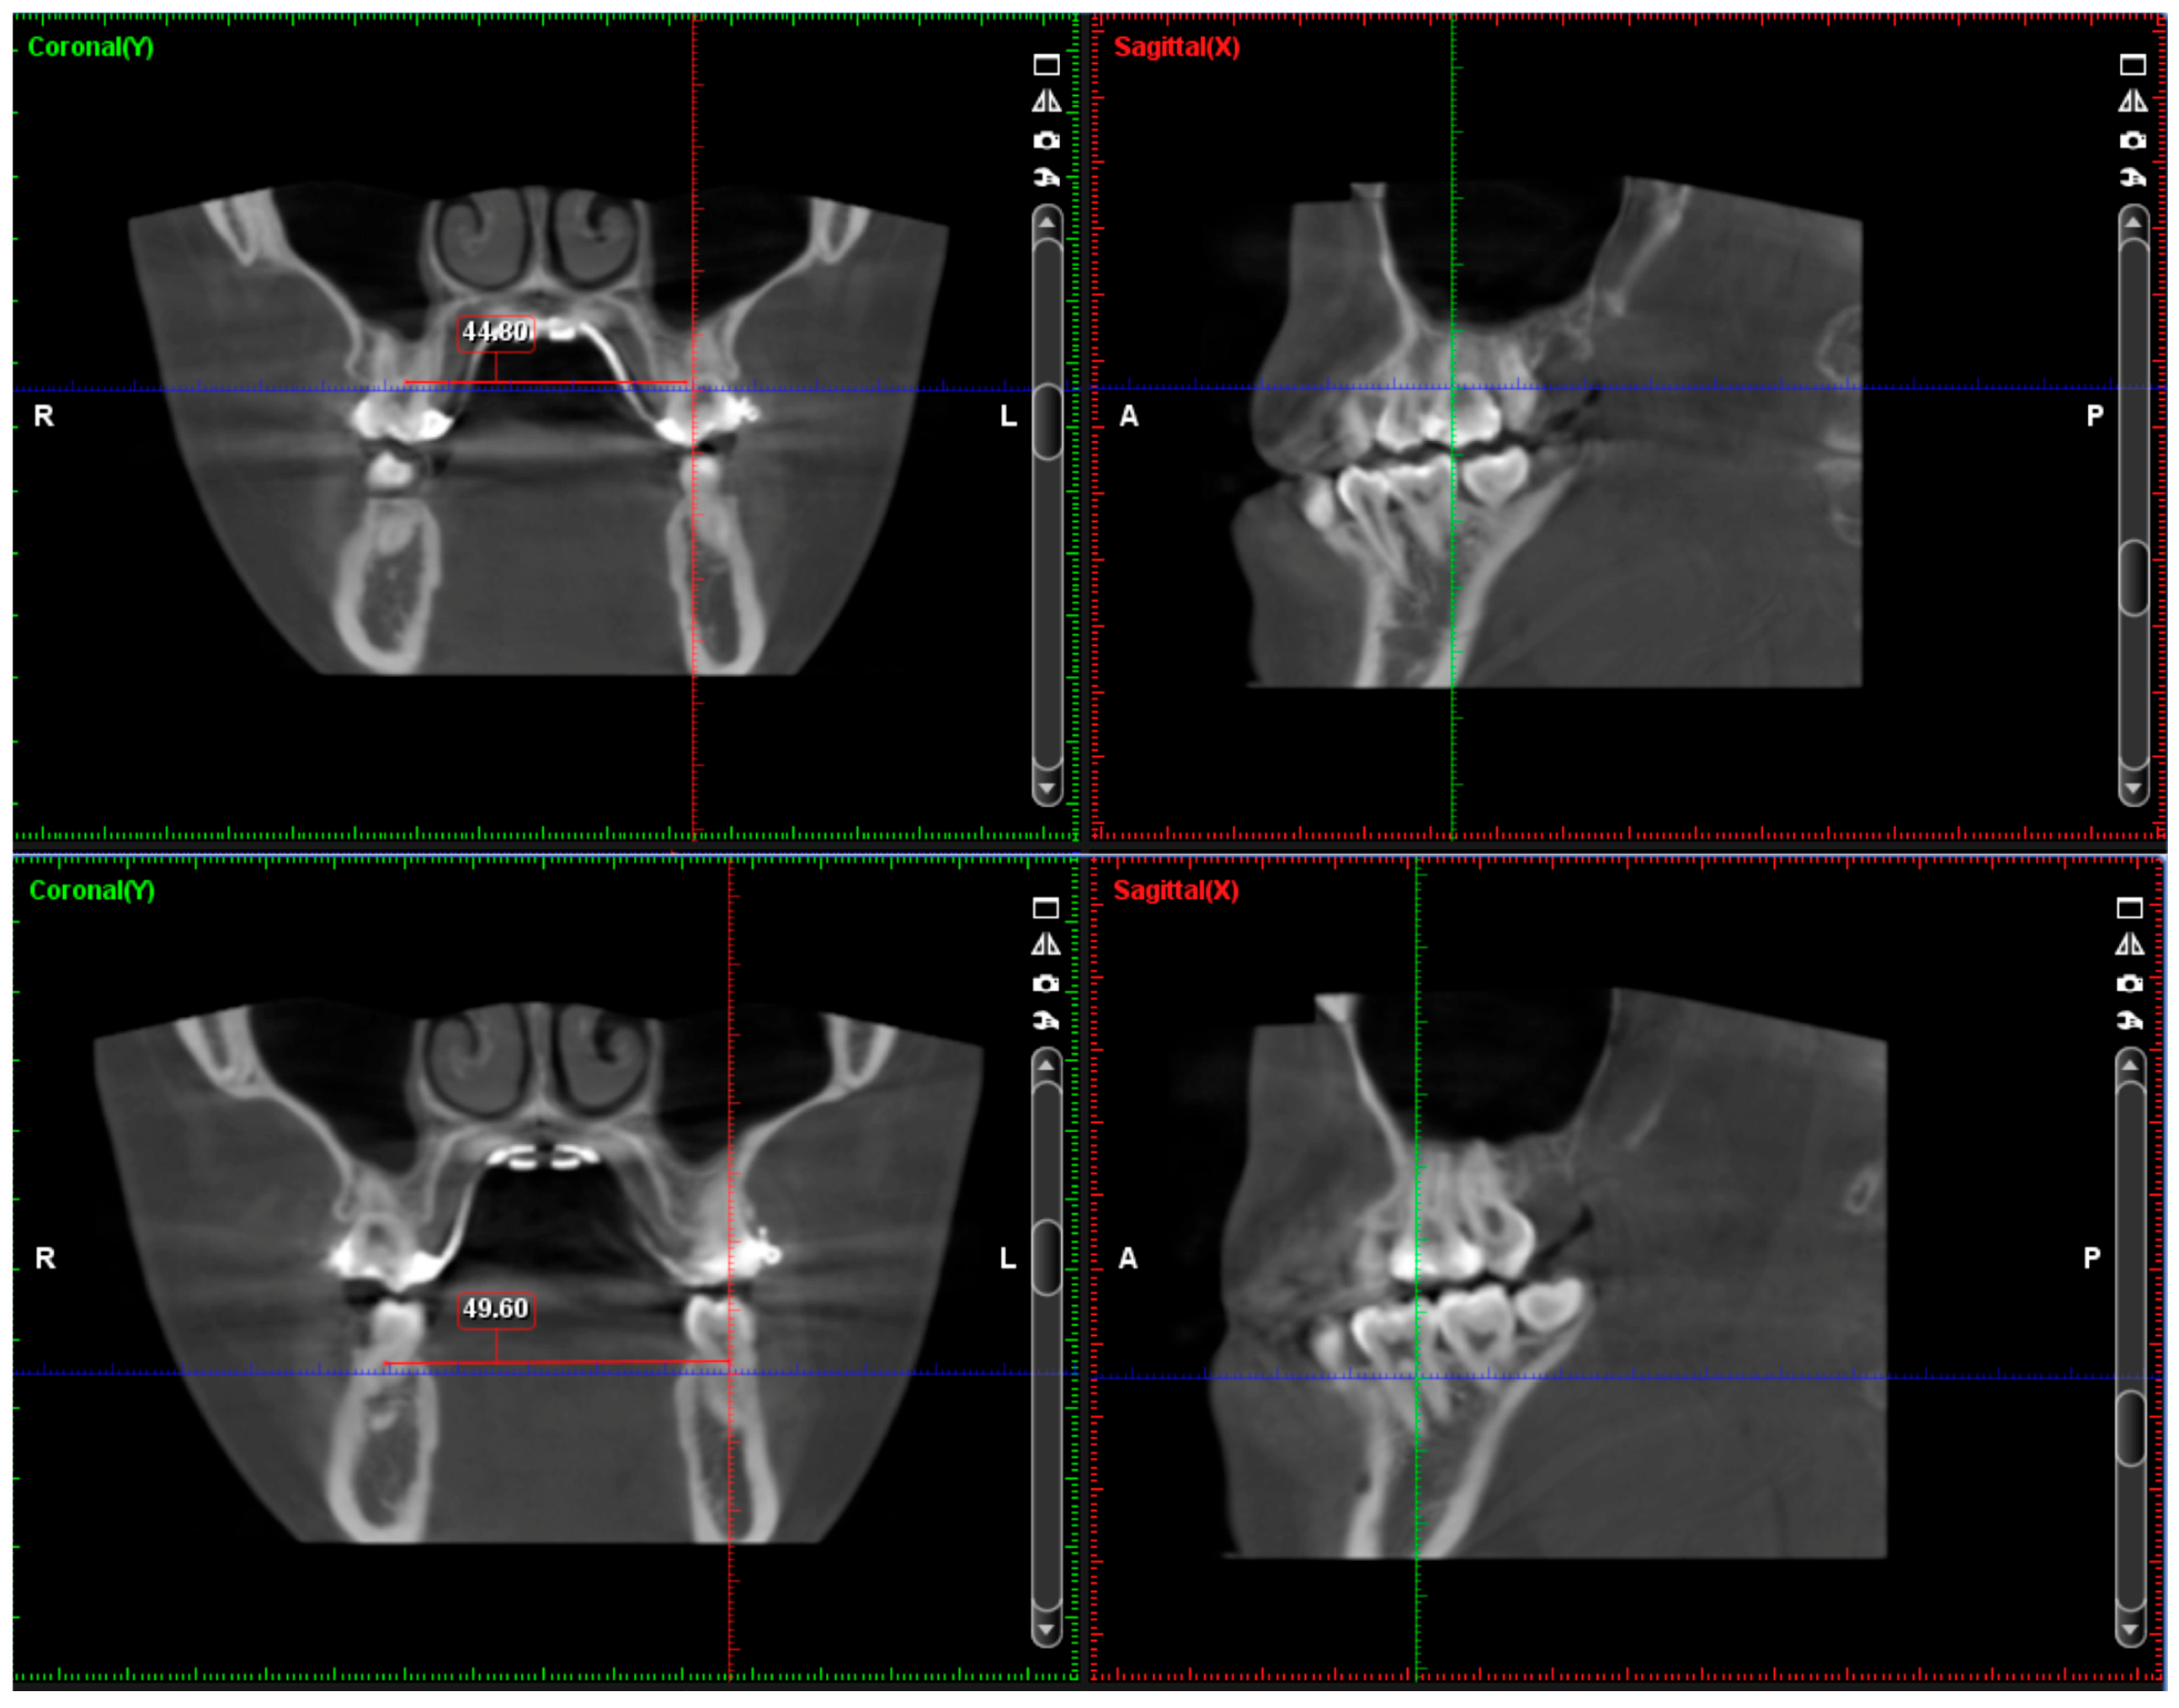

2.4. Treatment Progress

- Liao, Y.C.; Ho, K.H.; Wang, C.W.; Wang, K.L.; Hsieh, S.C.; Chang, H.M. Skeletal and dental changes after microimplant-assisted rapid palatal expansion (MARPE)—A Cephalometric and Cone-Beam Computed Tomography (CBCT) study. Clin. Investig. Orthod. 2022, 81, 84–92. [Google Scholar] [CrossRef]